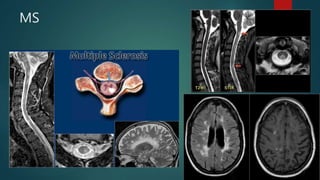

MS